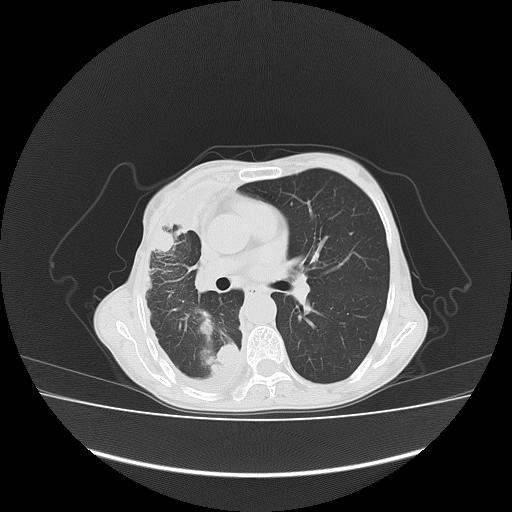

可见多发肺内病灶,且胸膜病灶较多有圆球状而非丘状,多考虑胸膜转移瘤伴胸腔积液,右侧胸廓缩小固定,且部分病灶呈丘状,尚不除外恶性胸膜间皮瘤伴肺内转移

右侧胸膜增厚,局部呈结节状增厚,右侧胸腔少量积液。双肺未见确切肿块影。纵隔未见淋巴结肿大。气管、支气管通畅。考虑右侧胸膜间皮瘤(恶性?)可能性大。不除外癌性胸膜炎。

恶性胸膜间皮瘤伴肺内转移可能性大;或胸膜、肺内均为转移瘤,左肺下叶亦见多发小结节影。

右侧胸廓塌陷,右侧胸膜广泛增厚并见多发胸膜结节,右侧少量胸腔积液并包裹。

右侧广泛胸膜增厚,局部呈结节状增厚,右侧胸腔少量积液。双肺未见确切肿块影。纵隔未见淋巴结肿大。气管、支气管通畅。考虑右侧胸膜间皮瘤(恶性?)可能性大。支持!

右胸腔结节均考虑来自胸膜(部分来源于叶裂),考虑胸膜间皮瘤或转移瘤.